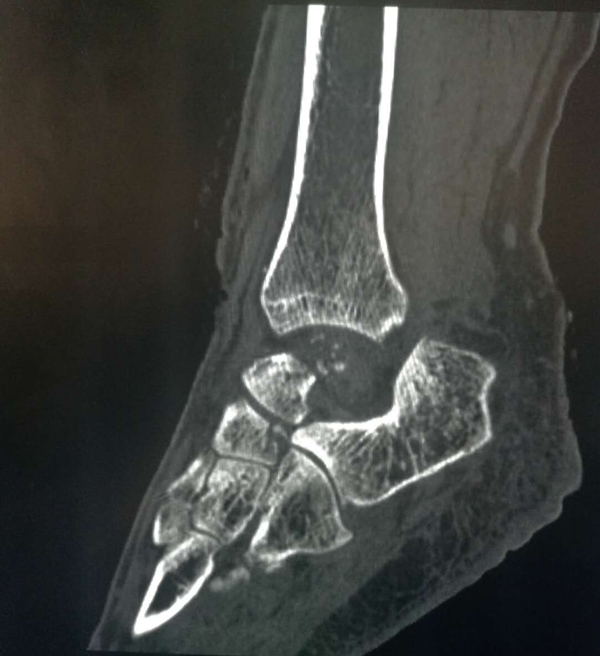

这位43岁的女性患者因不幸遭遇车祸,造成距骨粉碎骨折、脱出,导致左踝关节开放性脱位并距骨体缺损,踝关节活动受限,属罕见的病例。西安高新医院特邀我院骨二科贺西京教授会诊。贺西京教授根据患者病情,结合目前国际先进的3D打印技术,通过诊断,决定采用3D打印定制个体化距骨假体植入方案。由于患者左距骨丢失,贺西京教授团队通过患者右脚CT数据信息,镜像后的三维数字模型为患者“私人定制”量身定做左脚距骨,实施假体置入术,手术由贺西京教授亲自主刀,高新医院骨一科医生配合下,经过两个小时手术,成功将3D打印好的距骨精确无误的植入患者缺失部位,手术获得成功。

据贺西京教授介绍,距骨是人体踝关节的一个关键部分,主要支持脚向各个不同的方向上移动,是连接下肢和足部的枢纽,肩负重力传递和运动的耦联,是足部重要的功能单位。距骨缺失造踝关节功能丧失造成患者的踝关节屈伸功能不变。面对距骨的缺失,传统的治疗方法是进行踝关节融合术,会造成踝关节活动丧失,人工距骨置换可以实现踝关节和距下关节的运动,这就使足部可以上下左右的运动,使病人重新获得活动的能力。